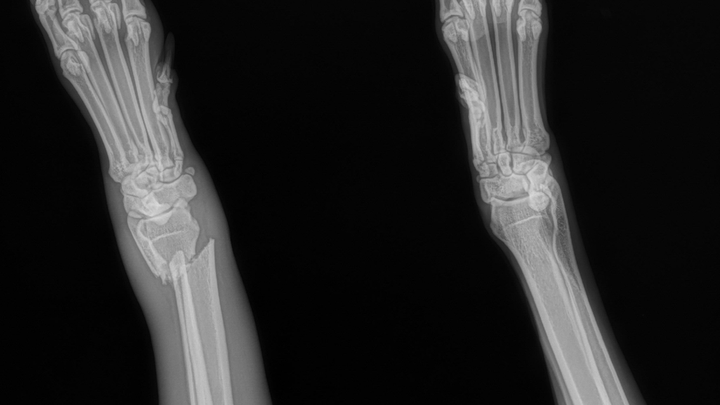

My dog Lu got loose and went on an adventure yesterday. She’s usually pretty crazy and gets herself hurt. I’d never imagine she’d hurt herself this bad. I took her to the vet today to see what they can do. She’s getting a splint and some pain meds to help with the pain, but unfortunately, that’s not going to be enough. Her carpus is broken in a weird spot and will require surgery. If it heals how it is with the splint, the doc said it would cause problems down the line with arthritis and consistent problems and pain. She’ll need surgery within a week; otherwise, it’s going to start to heal, and she’d need to get it rebroken. The good news is it’s a clean break and didn’t puncture the skin. Any help would be greatly appreciated.